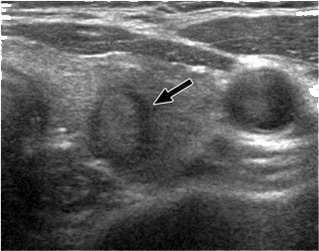

Ακόμα και όταν η βιοψία θυρεοειδούς δείξει καλοήθεια, το μέγεθος του όζου θα πρέπει να παρακολουθείται. Το υπερηχογράφημα παρέχει αντικειμενικό και ακριβή τρόπο ανίχνευσης μεταβολών στο μέγεθος του όζου. Ένας καλοήθης όζος (από τη βιοψία) που παραμένει σταθερός σε μέγεθος ή που φαίνεται να μικραίνει σε διαδοχικά υπερηχογραφήματα, δεν είναι πιθανό να είναι κακοήθης και να απαιτεί χειρουργική αφαίρεση. (Εικόνα Β, Γ).

Εικόνα Γ (Συμπαγής όζος στον αριστερό λοβό του θυρεοειδούς σε υπερηχογράφημα)